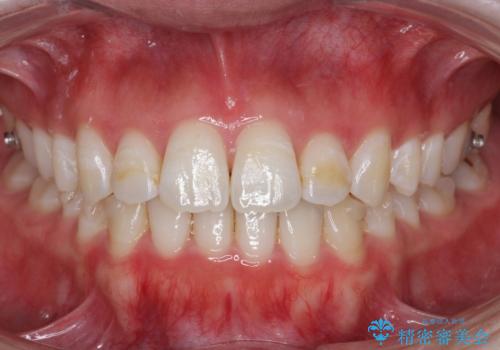

前歯のがたつきもしっかり治り、喜んでいただけました。

- インビザライン

- 1年